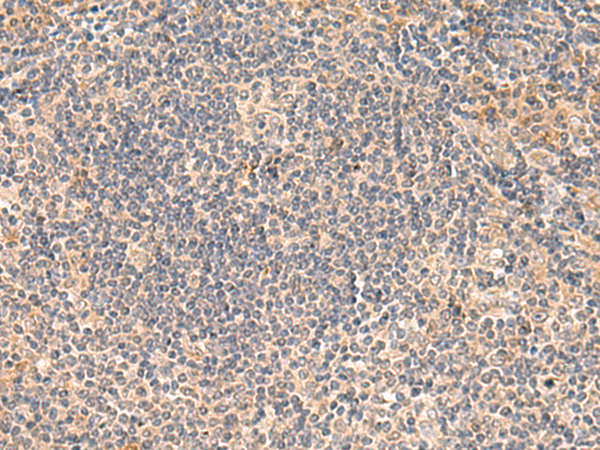

分类: 科研抗体货号: P10025别名: FDG; UNG3; HMUDG应用: IHC反应种属: Human, Mouse, Rat